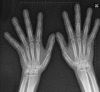

The primary hypertrophic osteoarthropathy (HOA) (pachydermoperiostosis) is a rare hereditary disease characterized by skin manifestations (pachydermia), digital clubbing and proliferation of periosteum (periostitis) with sub-periosteal new bone formation. We describe here a case who presented with seborrheic dermatitis and joint pain of both hands on work up matched satisfactorily with the complete form of primary HOA. The identification of secondary form being relatively common among clinicians and hence the importance of recognizing the primary form, which is a difficult to treat condition is discussed here.